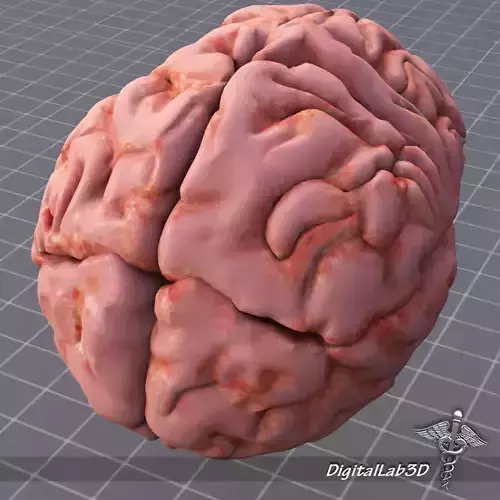

A 3D model of Human Brain External. Complete with color map and bump maps. This model is ready for 3d medical animation/presentation. This model is consist of different model conversions such as 3ds, max, maya, lightwave etc. This conversions can be open in any latest or old 3d software package. PSD Supporting file is included.

The brain is the center of the nervous system in all vertebrate, and most invertebrate, animals. Some primitive animals such as jellyfish and starfish have a decentralized nervous system without a brain, while sponges lack any nervous system at all. In vertebrates, the brain is located in the head, protected by the skull and close to the primary sensory apparatus of vision, hearing, balance, taste, and smell.